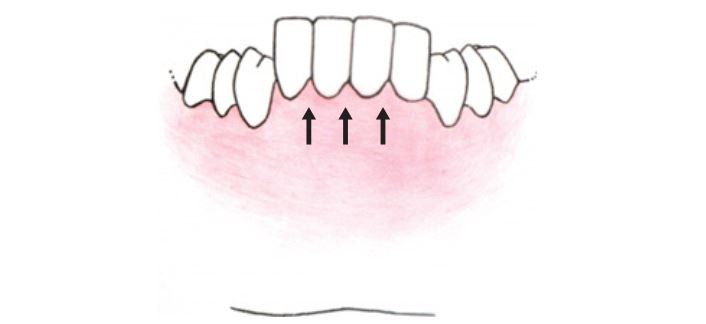

Răng mọc lên theo chiều dọc cùng với xương ổ răng cho đến khi chúng gặp 1 lực đối kháng ngang bằng với lực mọc răng.

Điểm chặn răng mọc thông thường là từ răng đối diện. Tuy nhiên chúng vẫn có thể bị cản lại bởi kháng lực từ môi, lưỡi hoặc bất cứ vật gì chèn vào giữa răng, chẳng hạn như ngón tay, ống điếu hay khí cụ phủ mặt nhai. Nhưng chỉ có lực nội tại từ hệ thống cơ nâng hàm là có thể kháng lại lực mọc răng.

Kích thước dọc cắn khớp (VDO) nói đến tương quan hàm dưới so với hàm trên theo chiều dọc khi các răng hàm dưới và răng hàm trên ở tư thế lồng múi. Mặc dù VDO xảy ra khi có đầy đủ răng trên cung hàm nhưng răng không phải là yếu tố quyết định của VDO. Hay nói rõ hơn, vị trí răng được quyết định bởi kích thước khoảng hở giữa hàm trên (cố định) với hàm dưới (được định vị bởi cơ).

Do vậy, tương quan hàm trên – hàm dưới sẽ quyết định răng mọc lên được bao xa.

Một yếu tố quan trọng thứ 2 cần nắm rõ về kích thước dọc là vị trí của răng theo chiều dọc có thể thích nghi với khoảng hở hiện có, chứ không phải là ngược lại, và khả năng răng sẽ mọc tiếp hay lún xuống luôn luôn xảy ra xuyên suốt.

Nếu lực từ răng đối lớn hơn lực răng đang mọc thì răng sẽ bị lún xuống cho đến khi lực mọc răng ngang bằng với kháng lực từ răng đối.